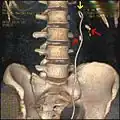

Rekonstruovaný 3D obraz z CT ureterálního stentu v levé ledvině (zvýrazněno žlutou šipkou). Jeden ledvinový kámen se nachází v močovodu (nižší červená šipka) a jeden v ledvině (vyšší červená šipka).